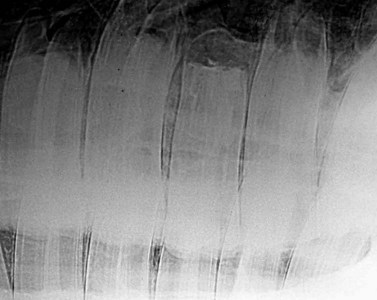

Adequate sealing of the resected apex has also been reported to have a major influence on the outcome of equine apicoectomies.21,28 To prevent the loss or disintegration of the apical seal, it is strongly recommended that an undercut is made with diamond-coated burrs on the apical aspect of each root canal (Fig. 22.13). Apical sealing can then be performed with self-curing, glass ionomer cement, amalgam, MTA or, less satisfactorily, with a resin-based calcium hydroxide cement (Fig. 22.14). Postoperative radiographs should be taken at this stage (Fig. 22.15) to ensure adequate pulp canal sealing is present.29 The surgical wound is closed in routine fashion. Antibiotic and anti-inflammatory drugs are administered for 3–5 days postoperatively.

image

Fig. 22.15 Postoperative X-ray of a 5-year-old Quarterhorse gelding after apical resection and endodontic treatment of 109.

(Reproduced from Simhofer H, Stoian C, Zetner K. A long-term study of apicoectomy and endodontic treatment of apically infected cheek teeth in 12 horses. The Vet J 2008; 178: 411–418. With courtesy of the editor.)14